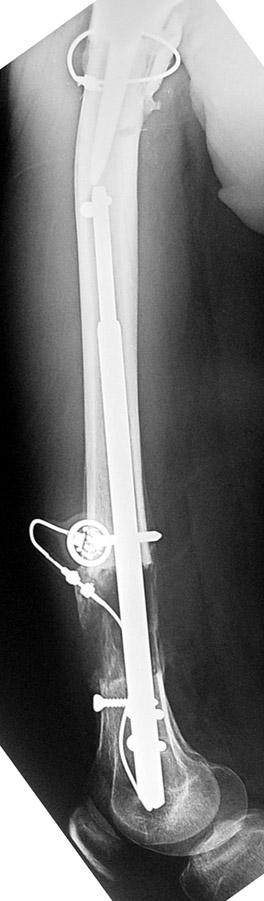

Case 2